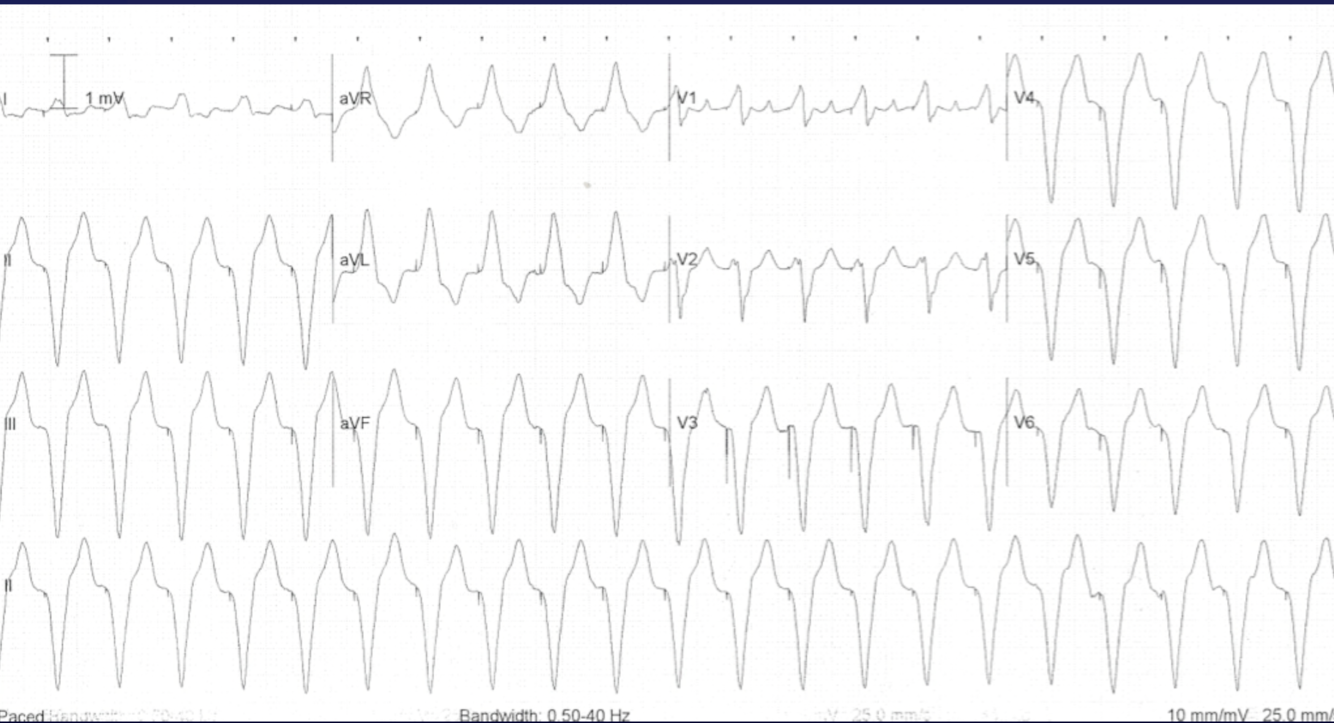

What rhythm?

VT